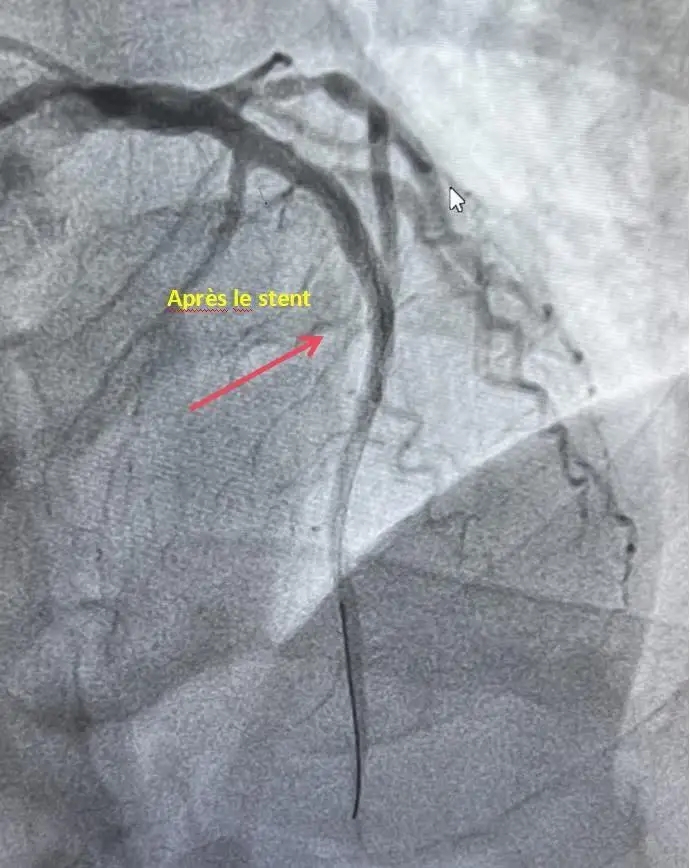

D’après les responsables médicaux de l’établissement, l’examen a mis en évidence une occlusion totale de la portion médiane de l’artère interventriculaire antérieure branche de l’artère coronaire gauche avec un flux sanguin classé TIMI 0. Une intervention de revascularisation a été immédiatement entreprise, permettant une reperfusion efficace grâce à la pose d’un stent. Le flux coronarien a ainsi été restauré à un niveau TIMI 3.